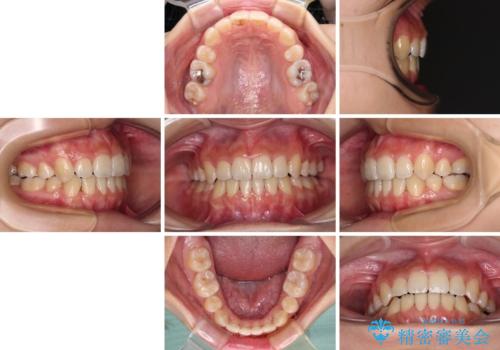

デコボコと八重歯の目立つ前歯 ワイヤー装置による抜歯矯正

奥歯の咬み合わせが理想的であり、歯の移動に時間のかかる出っ歯でもなかったため、2年程度で治療を終えることを目標としましたが、無事に予定通りの2年間で終えることができました。